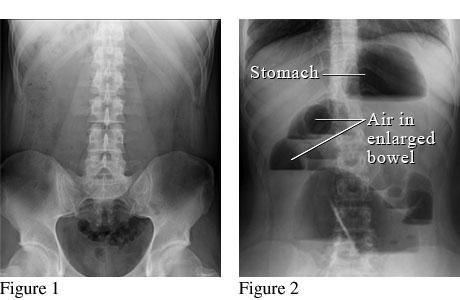

Abdominal X-ray of a bowel obstruction.

Courtesy of Intermountain Medical Imaging, Boise, Idaho.

Figure 1 shows a normal abdomen. Figure 2 shows air trapped in the bowels because gas, fluids, or food can't move through the bowels normally.